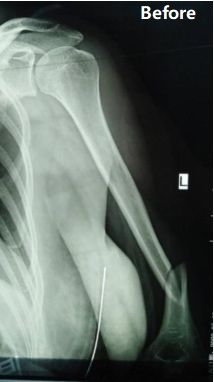

Case Sharing | Fratura do úmero diafisário médio a distal do terceiro

Resumo do Caso: Paciente do sexo feminino, 48 anos, foi diagnosticada como fratura do terço médio-distal da diáfise umeral esquerda (classificação AO: tipo B1).